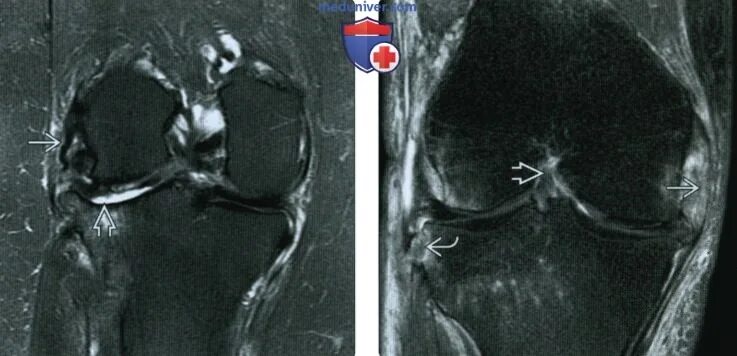

Мрт суставов химки